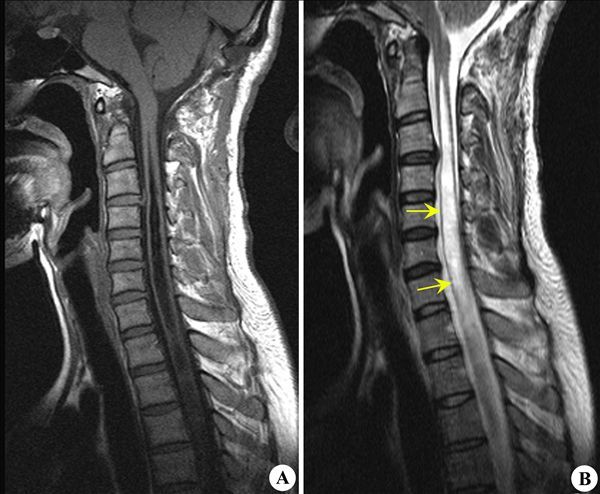

脊髓空洞症影像学表现

脊髓空洞症临床及影像学表现